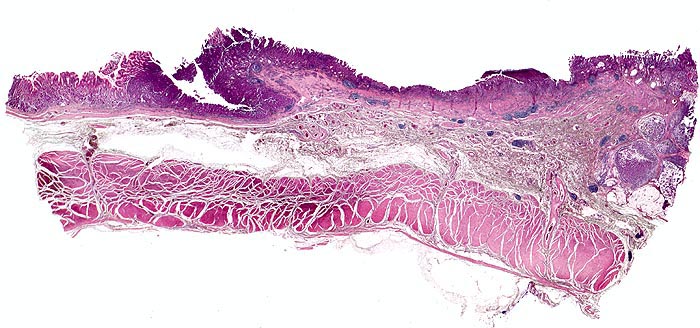

Morphologische Merkmale:

• Am unteren Ende des Präparates Antrummukosa mit mässiggradiger chronischer, geringgradig aktiver Gastritis und ausgedehnter intestinaler Metaplasie (Becherzellen).

• Weiter oben Invasion der Magenschleimhaut durch ein teils solides, teils drüsenbildendes Adenokarzinom mit stark atypischen Tumorzellen.

• Fokale Erosion des Karzinoms bedeckt von fibrinoleukozytärer Membran.

• Tumorinfiltration der Submukosa an der oberen Präparathälfte.

• Der invasive Karzinomanteil zeigt teilweise muzinöse Differenzierung (teils siegelringzellige Tumorzellen schwimmen in extrazellulären Schleimseen).

• Tumorfreie Lamina muscularis propria.